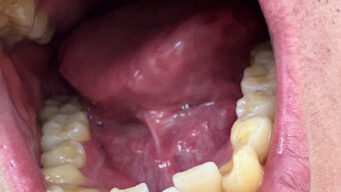

嫌儲 13歳の時に失明した男性、目に歯を埋め込む事で視力を取り戻す。ハハッ